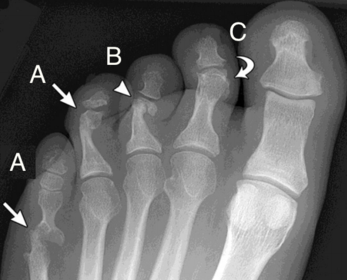

| What disease is this? What is shown by A, B and C? | Psoriatic arthritis. A = destructive changes B = Pencil in cup deformity C = IPJ fusion |